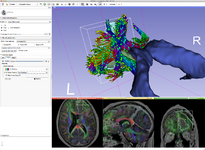

The community of Slicer developers is proud to announce the release of Slicer 4.0.

- Slicer 4.0 includes a major overhaul of the user interface, improved and simplified workflows for major tasks, simplified procedures for developers, and improved Python support.

Slicer is a community platform created for the purpose of subject specific image analysis and visualization.

- Multi-modality imaging including, MRI, CT, US, nuclear medicine, and microscopy

- Multi organ from head to toe